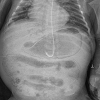

Gastric pneumatosis in a preterm infant: A case report

Paramesh Sreekumar, Prince Raj, Arjun Chandra Dey, Emad Shatla, Martin Thomas Corbally

24